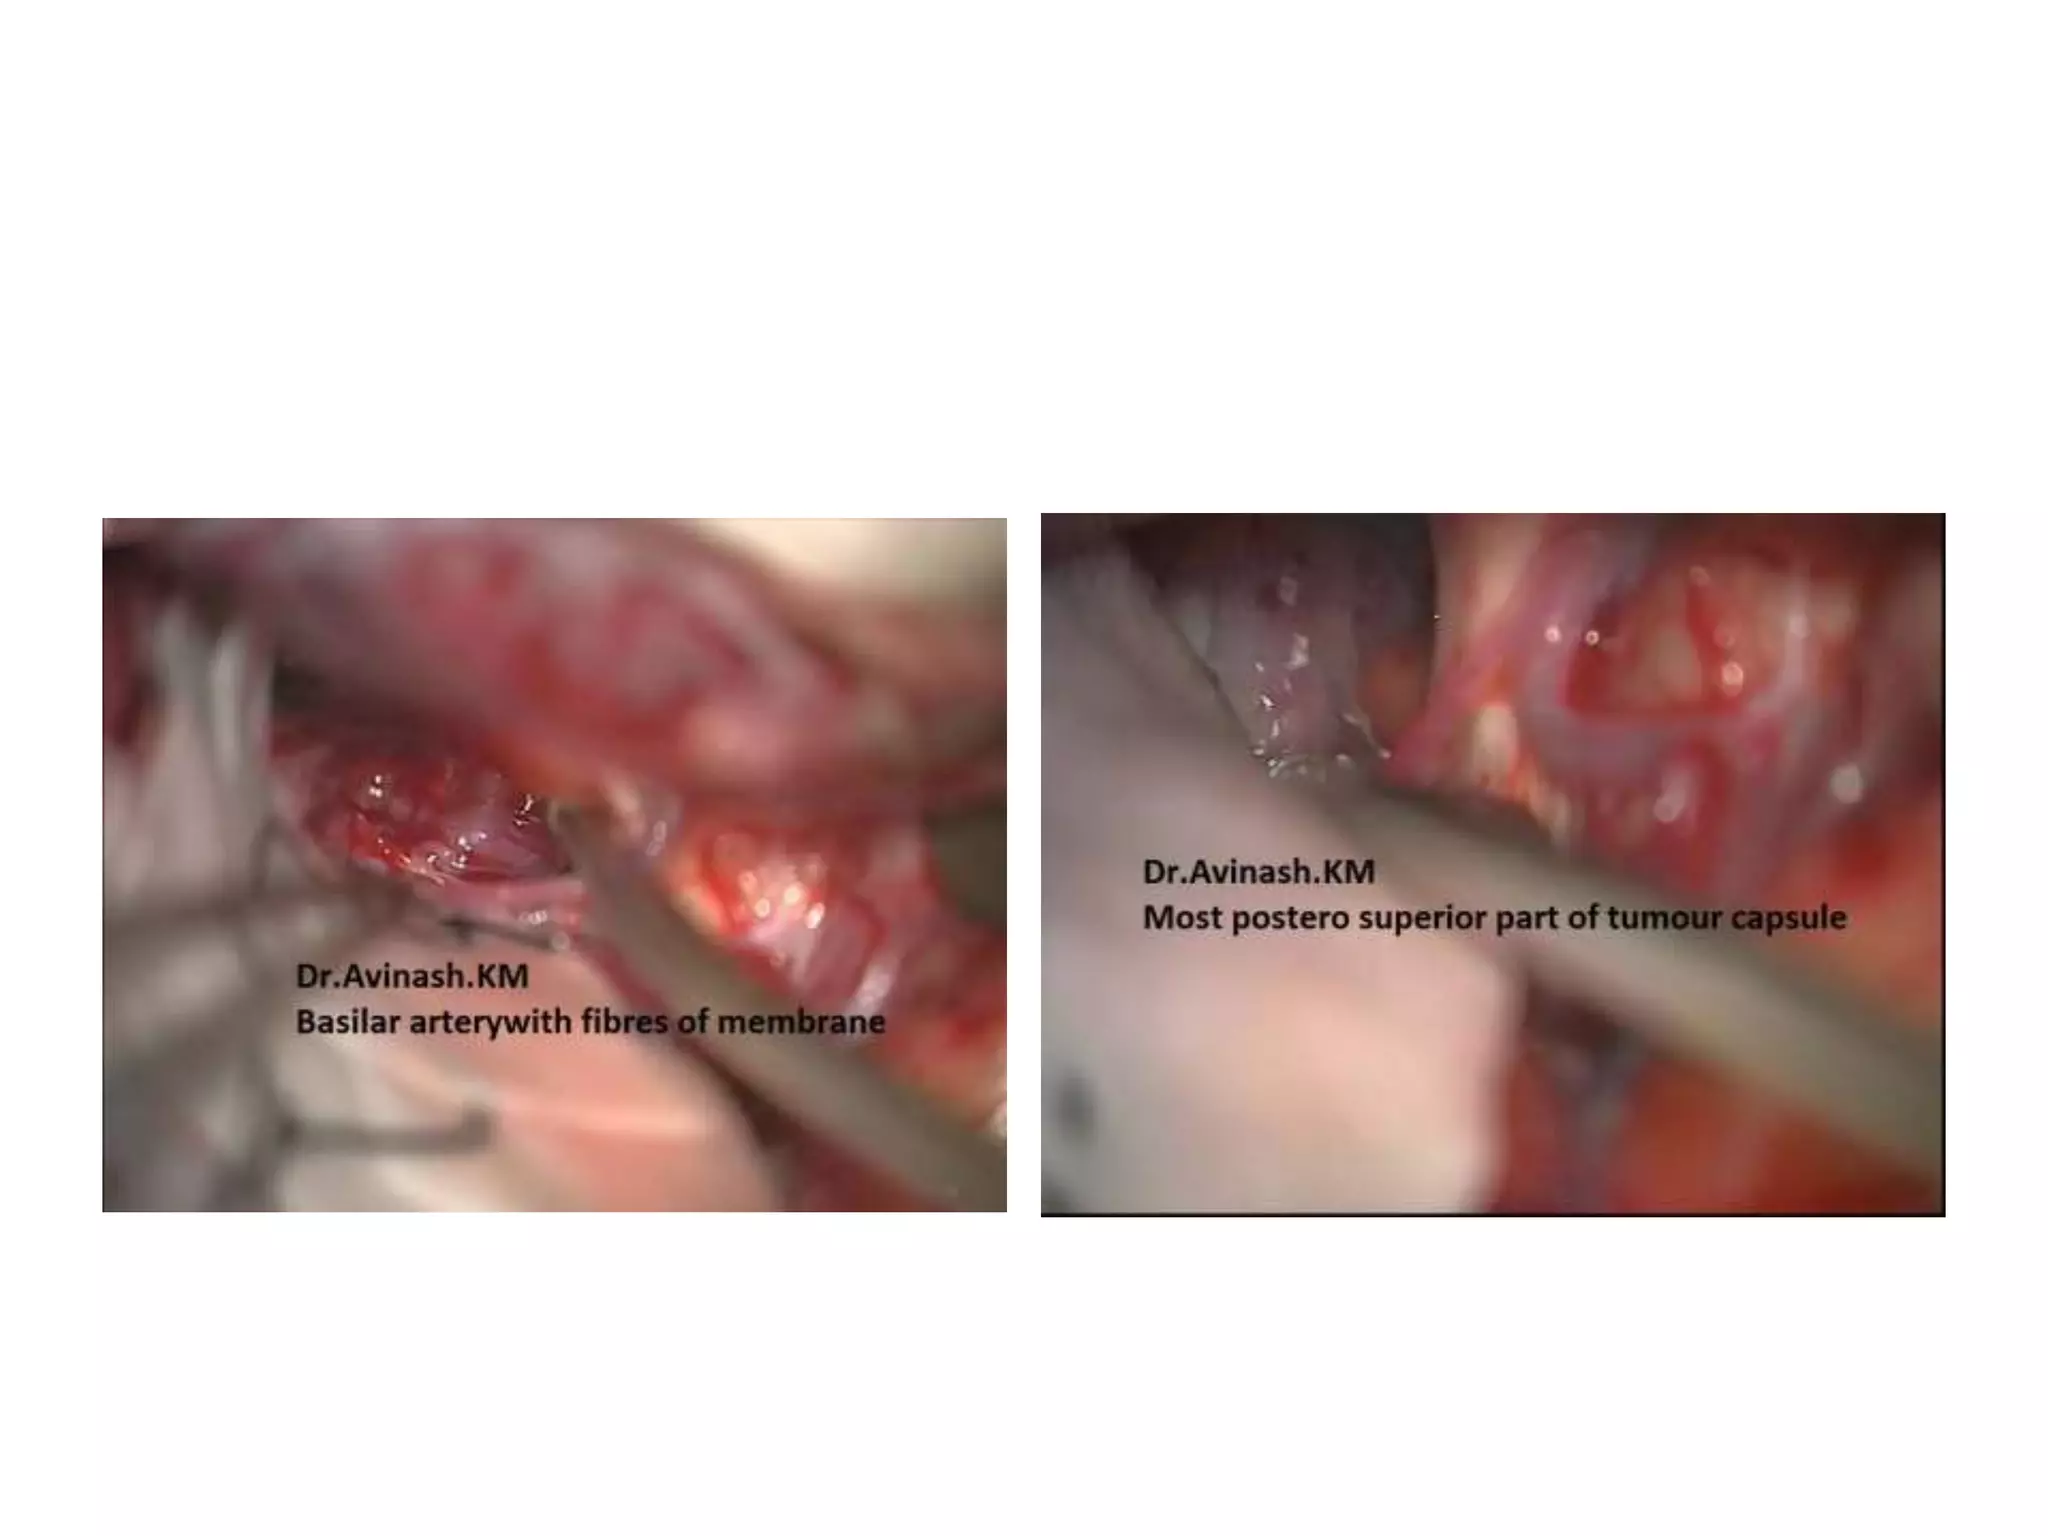

a,b Intraoperative image of the fenestration of deep cystic membrane using different microsurgical

instruments (forceps and scissors). Asterisks posterior communicating artery and anterior choroidal

artery. c Fenestration of the cisternal layer (cross Liliequist’s membrane). d Intraoperative picture at the end

of the procedure